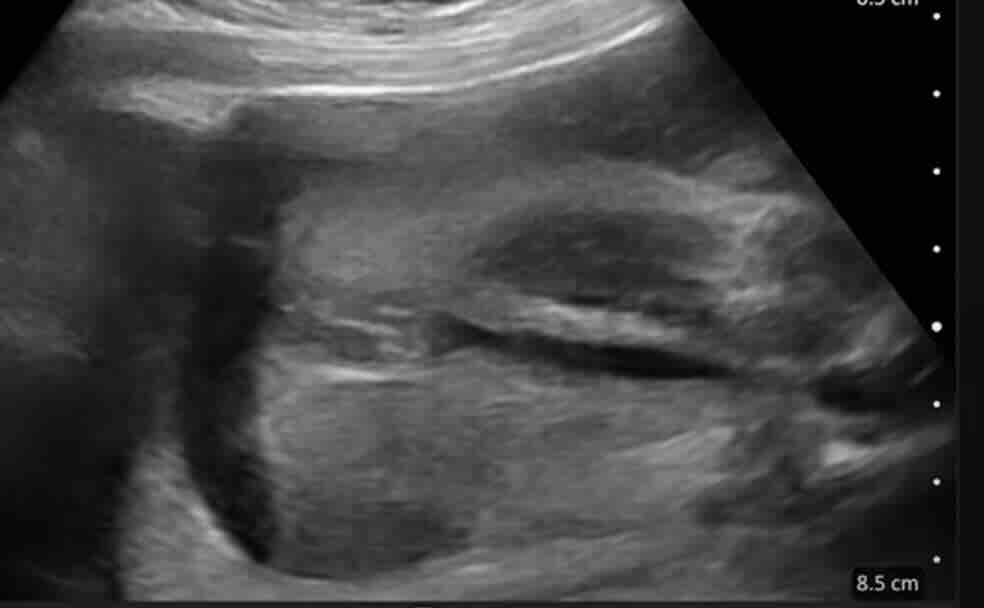

Rahim filmi, rahim iç boşluğunu ve tüplerin açıklığını değerlendirmek için yapılan özel bir röntgen görüntüleme yöntemidir.

Bu işlem sırasında rahim içine kontrast madde verilir ve röntgen altında görüntü alınır. Eğer tüpler açıksa kontrast tüplerden karın içine yayılır. Eğer tıkanıklık varsa kontrast ilerlemez ve bu durum net şekilde görülür.